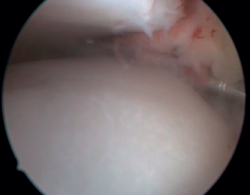

La confirmación del PAT se hará mediante visión directa durante la exploración artroscópica (Figura 4). Esta técnica permite visualizar toda la articulación, evaluar el estado del cartílago articular, los ligamentos, detectar la presencia de adherencias capsulares, sinovitis, engrosamiento sinovial, cuerpos libres, etc. Además, nos permitirá realizar test funcionales para poner de manifiesto posibles inestabilidades asociadas o valorar cómo se pinzan las partes blandas causantes de dolor. La presencia de lesiones del LTFA es, en nuestra experiencia, muy frecuente.

Figura 4. Pinzamiento anterolateral de partes blandas en un paciente con lesión concomitante del ligamento talofibular anterior, al que se le hizo una reparación artroscópica asociada a la resección del pinzamiento.